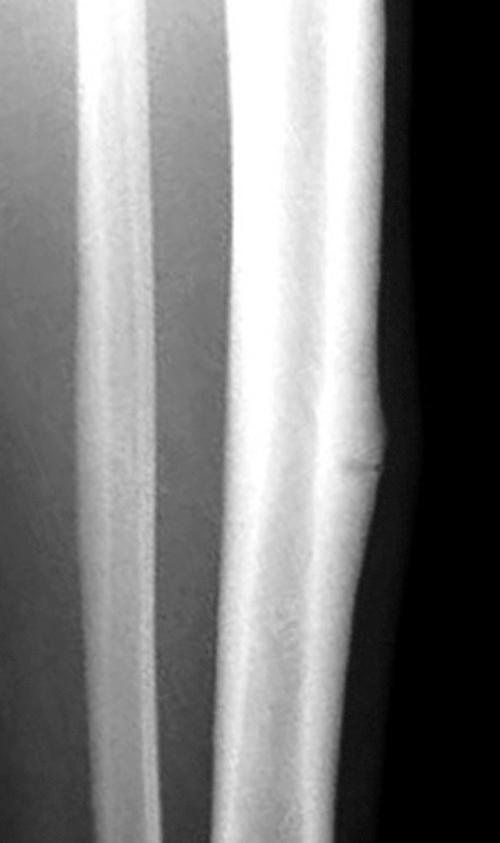

Leg pain in athletes can be caused by many conditions, with the most frequent being medial tibial stress syndrome; chronic exertional compartment syndrome, stress fracture, nerve entrapment, and popliteal artery entrapment syndrome are also considerations. Conservative management is the mainstay of care for the majority of causes of chronic lower leg pain; however, surgical intervention may be necessary.

Chronic lower extremity pain in athletes includes a wide differential and can pose diagnostic dilemmas for clinicians.